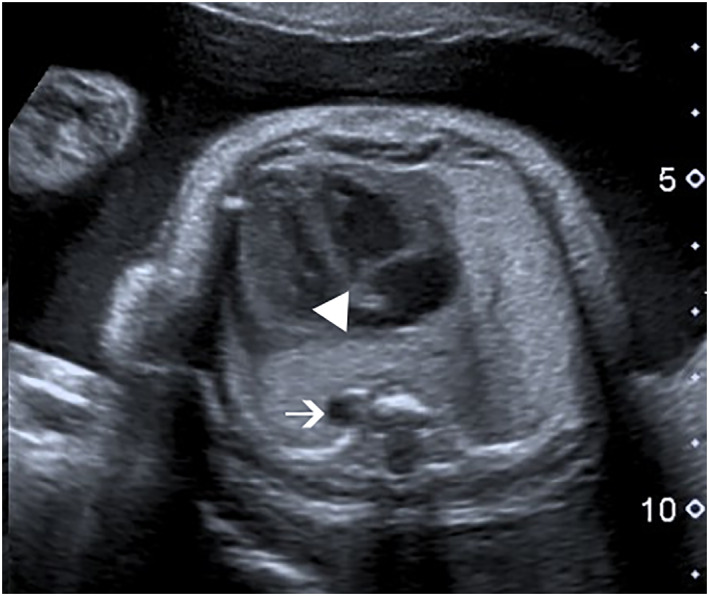

Results: One case was diagnosed by magnetic resonance imaging (MRI) and two by ultrasound with MRI confirmation. Two patients were referred to our center for diaphragmatic hernia (with a sac in one case). The third patient was referred because of a thoracic aorta on the very left side. After birth, costal anomalies, agenesis of the body and tail of the pancreas, and an associated pelvic kidney were diagnosed. All neonates were presented with acute respiratory distress; two had a favorable outcome, and the third died within the first few days of life.